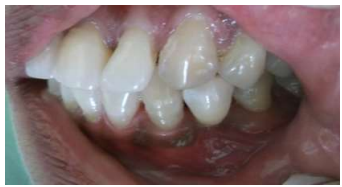

The apical opening of the pulp canal was cleaned, slightly enlarged, and sealed with resin composite. A modified ridge lap design was given to cervical area to facilitate cleaning and appearance of emerging profile. The apical portion of the root was removed to facilitate proper positioning of the tooth in an edentulous area. Intracoronal round 0.001” braided wire was inserted into the prepared tooth and bonded with composite. It was then bonded to the adjacent teeth using light cure composite. Finishing and polishing procedures were carried out using composite finishing discs and stones (Fig 02 - 05).

Figure 4: Composite (Ribbond) Application and Curing

Figure 5: Natural tooth Pontic in Place

Oral hygiene instructions were given to the patient. The first recall appointment was made after 1 week. The patient’s sanguine countenance was result of the achieved desired esthetics improved ease of biting without any discomfort.